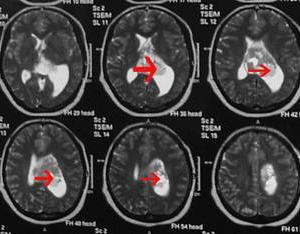

輔助性檢查包括顱骨X線平片檢查、腦CT、MRI、腦血管造影、腦超聲檢查等。其中腦CT與MRI是當前對腦瘤診斷最具有價值的檢查方法,陽性率達95%以上,對明確腫瘤的部位大小、範圍具有重要價值。近年來套用正電子發射斷層掃描(PET)可顯示腫瘤影像和局部腦細胞功能活動情況。

值得一提的是腦成像技術未問世前,腦血管造影對確定腫瘤的部位和性質是有價值的,目前已被CT、磁共振等腦成像技術所取代,僅在懷疑腦膜腫瘤或血管性異常時始使用腦血管造影。